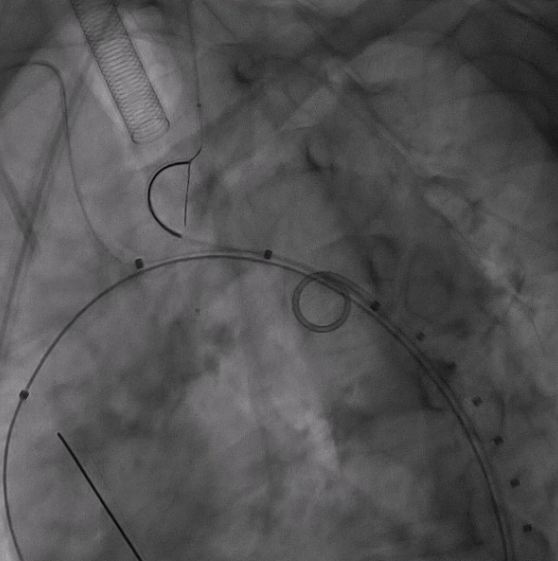

5. 支架释放与球囊预扩

释放支架主体,之后,头端后释放打开后将支架输送系统缓慢撤出。

分别经分支导丝送入球囊扩张支架分支覆膜部分,确保贴附良好。

6. 裸支架置入,球囊后扩张

于无名动脉、左颈总动脉及左锁骨下动脉开口位置处释放裸支架,维持血流通畅。

球囊后扩,优化支架形态及贴壁性,减少内漏风险。

术后造影显示,主动脉支架定位精准,三分支支架内血流通畅,夹层内仅有少量膜渗情况。从手术即刻效果来看,该治疗方案达到了预期目标,有效修复了主动脉夹层,恢复了血管的正常解剖结构和血流动力学状态。